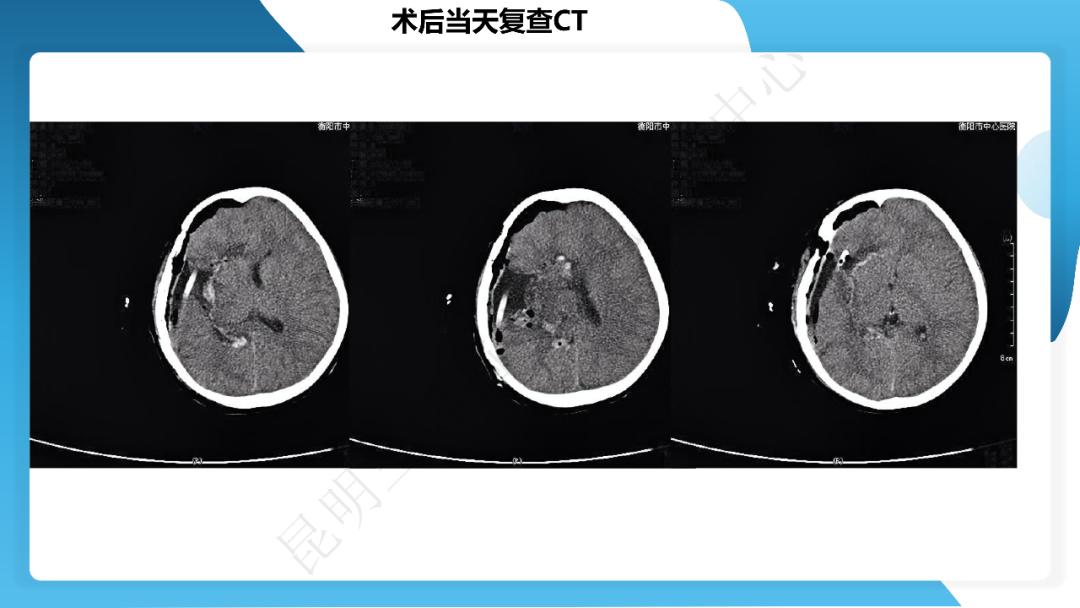

《「痫停」信步》癫痫治疗病例荟萃第四十一期---大脑半球离断术治疗 Rasmussen 脑炎引起的难治性癫痫一例